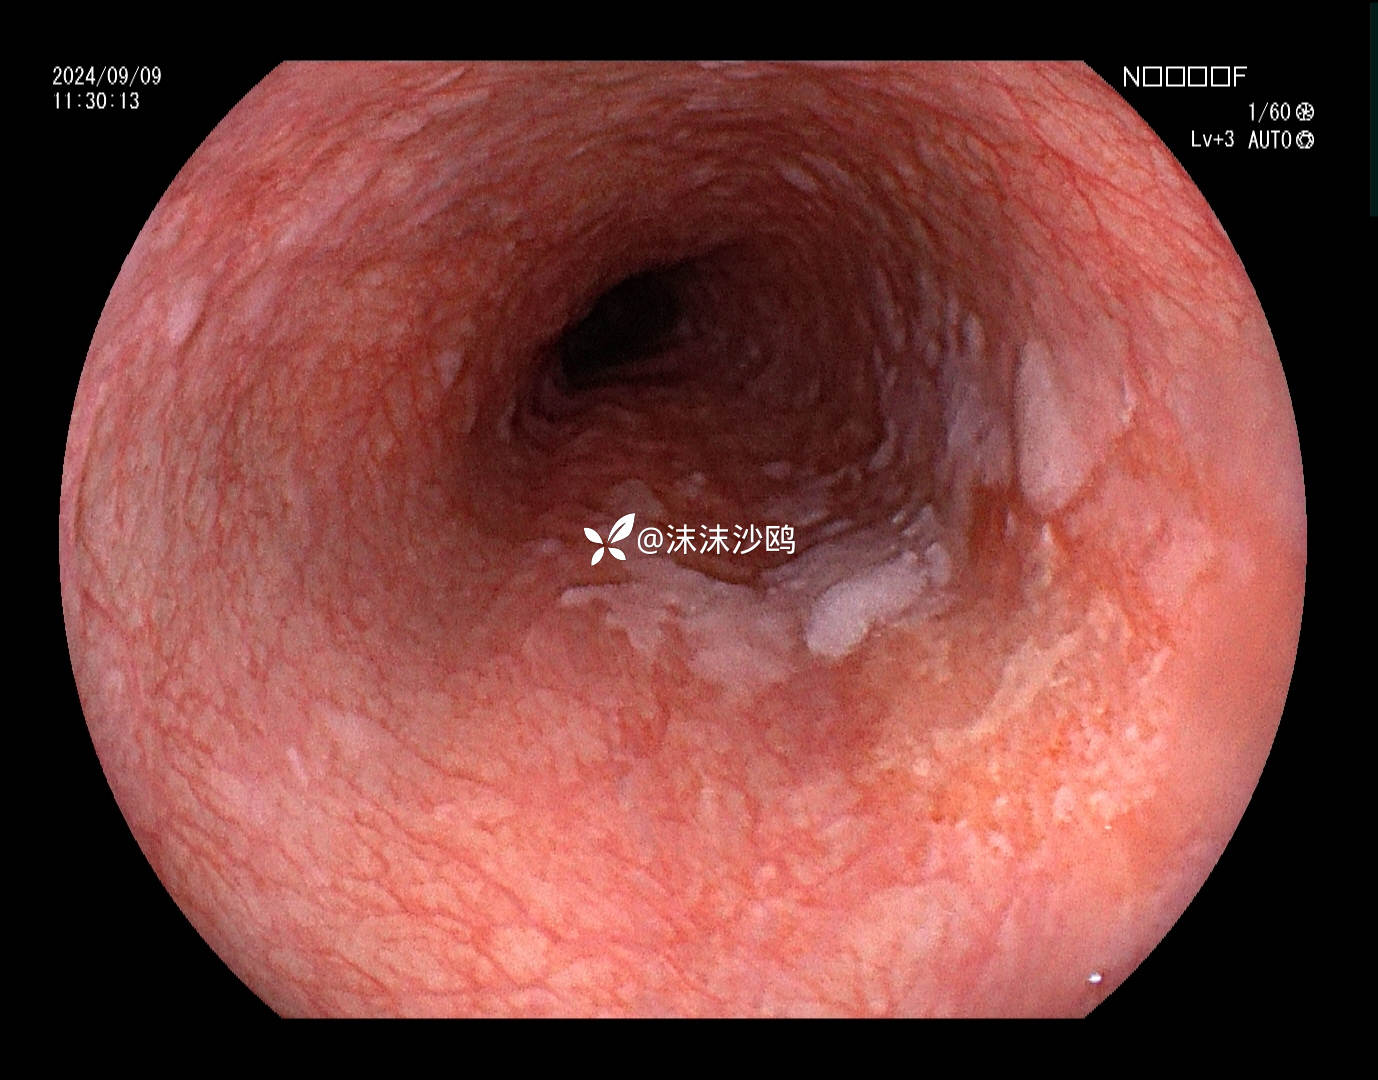

老年男性,腹胀不适门诊行普通胃镜检查。距门齿30cm见片状粘膜粗糙发红,呈0-II b型病灶。

距门齿30cm见片状粘膜粗糙发红,大小约2cm,形态0-II b型

该患者平素无明显症状,吸气注气观察病灶延展性,柔软度可,白光观察粘膜呈现发红粗糙,BLI放大观察呈现明显茶褐色,可见B1型血管,局灶可见紊乱生长的B2型血管,并见AVA区域,感觉小于0.5mm。镜下考虑浸润深度,不超过SM1,应该有内镜下D的可能性。等病理结果,希望符合内镜诊断。